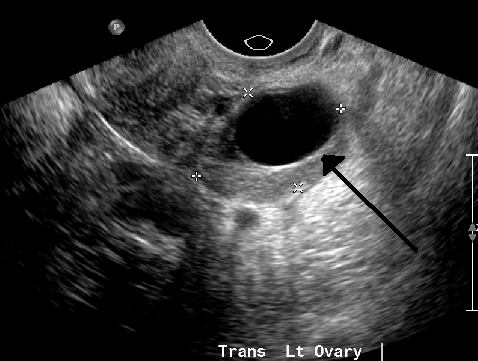

Dermoid cysts, though rare and typically noncancerous, are unique due to their varied tissue content. Their progressive expansion over time means that even if initially asymptomatic, they can eventually exert enough pressure to cause significant discomfort. Diagnostic imaging, such as ultrasounds or MRIs, is essential for confirming their presence and monitoring their growth.

While endometriomas are benign, they can be quite painful and complex to manage, often indicating a more severe stage of endometriosis. Early detection through imaging is critical not only for alleviating symptoms but also for preventing potential complications, which may include impacts on fertility. The cyclical nature of the pain they cause can also be a distinguishing characteristic.

Upon presentation to a medical facility, diagnostic steps typically include a pelvic exam and ultrasound to confirm the rupture and assess any associated bleeding. In certain cases, a CT scan may also be utilized to gain a more detailed view of the abdominal cavity. For postmenopausal patients, a CA-125 blood test might be conducted to rule out potential malignancy, given that symptoms can sometimes overlap.

For small, asymptomatic cysts, a common initial strategy is “watchful waiting.” This conservative approach involves regularly monitoring the cyst through periodic ultrasounds, typically every three months, to track any changes in size or characteristics. Given that most functional cysts resolve spontaneously within a few menstrual cycles, watchful waiting allows natural healing while ensuring no concerning developments are overlooked. During this period, over-the-counter pain relievers can be used for any mild discomfort, and avoiding strenuous activities can help minimize complication risks.